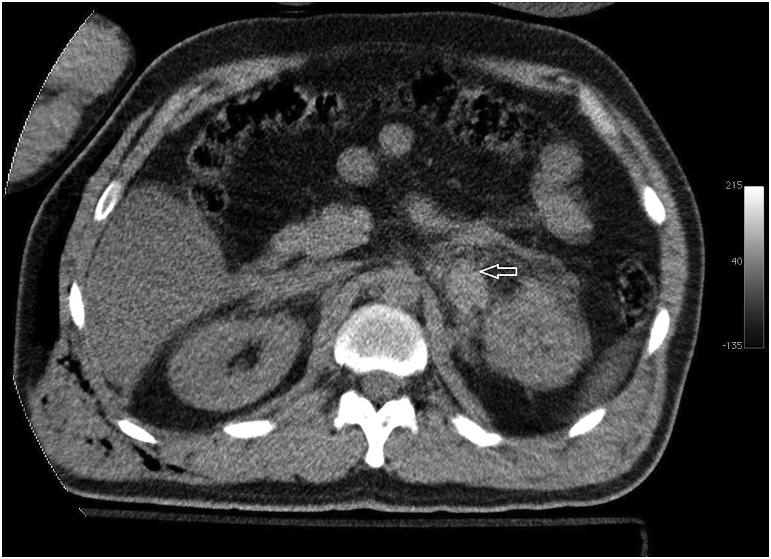

Adrenal hemorrhage following blunt abdominal trauma is extremely rare. Most of the lesions are unilateral and right sided. Although often asymptomatic, life-threatening adrenal insufficiency may develop in the bilateral adrenal gland hemorrhage. Isolated adrenal injuries are very rare. They are often associated with other organ injuries. The mortality rates of patients range from 7% to 32%. In this report, we present the computed tomography and magnetic resonance imaging findings of unilateral adrenal hemorrhages in two patients with a history of fall from a height.

钝性腹部创伤后肾上腺出血极为罕见。大多数病变为单侧且位于右侧。虽然通常无症状,但双侧肾上腺出血可能会发展为危及生命的肾上腺功能不全。孤立性肾上腺损伤非常罕见。它们常与其他器官损伤相关。患者的死亡率在7%至32%之间。在本报告中,我们展示了两名有高处坠落史患者单侧肾上腺出血的计算机断层扫描和磁共振成像结果。